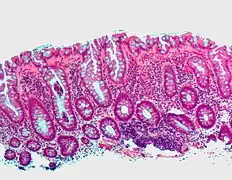

| Tubular adenoma | 2% at 1.5 cm[12] | Low to high grade dysplasia[13] | Over 75% of volume has tubular appearance.[14] | ![]() |

Microvesicular hyperplastic polyp. H&E stain.